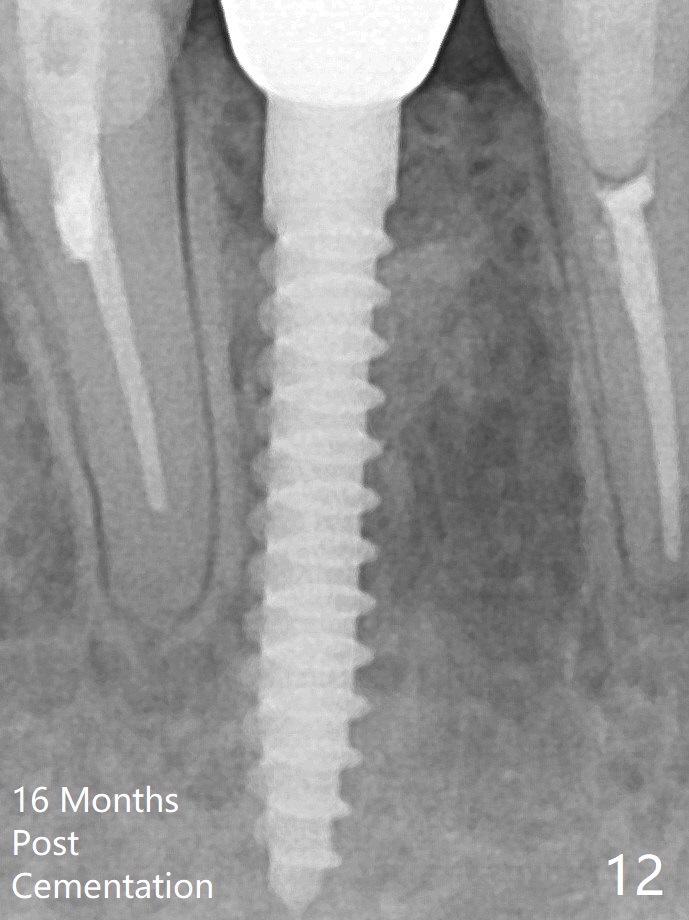

A drawback of implant planning at #25 is not to use a preop PA (Fig.1 (^ fracture line)). The initial trajectory seems to be alright (Fig.2 (red line: socket; D: 1.2 mm drill)), but a 2.5x14(2) mm implant placed is close to the tooth #26 (Fig.3 (allograft having been placed)). The latter may be related to more bone loss in the distal crest 3.5 months postop (Fig.8) and more severe distal papillary recession (Fig.9 *). The meisal bone seems to be wider. The bone density increases at the levels of the non-thread and thread portions of the implant (in the original socket) nearly 10 months post cementation (Fig.11 *, <). The bone density increase is related to deep placement of the implant. There is no bone loss 16 months post cementation (Fig.12).